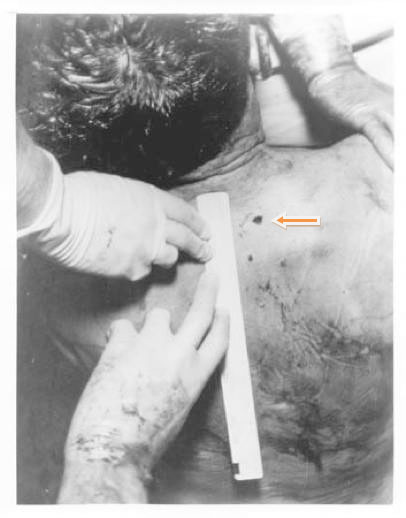

The Back Wound

In the autopsy photograph (Appendix 5, Figure 2), the back wound appears to lie at about T1 (i.e., the first thoracic vertebra), just above the level of the scapular spine. This seriously disagrees with the T3 on the death certificate, which was prepared by Admiral Burkley (p. 221). Two individuals even placed it at T4: James Jenkins and, in a conversation with me, John Ebersole (who practiced my specialty of radiation oncology). For normal anatomy see Appendix 5, Figures 3A and 3B. As is well known, the back wound in the autopsy photo is noticeably higher than the holes in the shirt or jacket. Furthermore, the wound on the Autopsy Descriptive Sheet (prepared by Boswell at the autopsy; see Appendix 5, Figure 4) appears to lie well below T1—at least as low as T2, if not even lower. An online source assigns a typical level to the scapular spine as T3 (manualmed.blogspot.com/2008/09/thoracic–spine-landmarks.html). In fact, any level for this back wound below T1 would destroy the SBT (because the back wound would then be lower than the throat wound). However, Boswell later elevated this wound, thus abandoning his earlier, on-site observation. Somewhat amusingly, on this second occasion Boswell elevated this back wound far too high (compared to the autopsy photo), actually into the neck, which only raises questions about either his memory or his honesty. (See these two incompatible placements by Boswell at Inside the ARRB by Douglas Horne, Volume I, Figure 56.) A likely explanation for the discrepancy between the photo and the Descriptive Sheet is post-autopsy (illicit) photo alteration in the dark room. Curiously, this is the precise autopsy photo that displays an anomalous object on the back (not noted by prior investigations), which might be a leftover image from photographic tampering. Further discussion of this follows below.

Another point is worth emphasizing: physical tests showed no copper deposits on the shirt or on the collar (in the front), even though they were present on the back of JFK’s jacket. This is consistent with a metal projectile as the source for the back wound, but it is inconsistent with a metal projectile through the front of the shirt. On the contrary, the slits had probably been created by the nurses’ scalpels. In an interview in 1971, Carrico actually confirmed this to Harold Weisberg—see Weisberg’s Subject Index File, under “Carrico,” items 02 and 03. (Jerry McKnight reports this.) In addition, based on my personal observations at the Archives, some cloth is missing from both the back of the shirt and the back of the jacket, but none appears missing from the slits at the collar. Furthermore, although McAdams claims that a throat wound at C7/T1 is feasible, he totally ignores the anatomic conundrums in the horizontal plane. (For pertinent, and rather devastating, anatomy and radiology images see Appendix 5, Figures 5-7.) For a more precise vertical level for the throat wound see MIDP (p. 228). James H. Fetzer has also offered a concise analysis of this evidence in “Reasoning about Assassinations,” which he presented at Cambridge and then published in an international, peer-reviewed journal (The International Journal of the Humanities (2005-2006), Volume 3, Issue 10, pp. 31-40).

McAdams asks a pertinent question about the SBT: If a bullet struck the back, then where did this bullet go? He disregards a possible deflected fragment (from the street) that might have caused this wound. Such a bullet ricochet (possibly more than one) was reported by multiple eyewitnesses (6H238, 7H291, 7H507-515, MIDP, p. 36, and No More Silence by Larry Sneed, p. 145). Because this option—of a deflected projectile (not necessarily an entire bullet)—even appears in the WC ancillary volumes, McAdams has no excuse for omitting it.

McAdams assumes that the location of these holes supports the SBT. While at the Archives I had a tall male wear the jacket (while standing). He was an inch or two taller than JFK. What was surprising was how low these holes lay. The bullet holes in the shirt and jacket were nearly at the same level (as one another); the center of the hole in the shirt lay 7 ½ centimeters inferior to the horizontal shoulder seam. It also lay about 3 centimeters inferior to the top of the scapula. The clothing images may be seen at here and here. McAdams cites a photographic study that shows the jacket elevated during the motorcade here. Although it is likely that the jacket was elevated at the critical moment, this study surprisingly does not estimate how much it was elevated. This study concludes: “As a direct result, the ‘low’ bullet holes in John Kennedy’s shirt and jacket are not accurate indicators of the entry location, which must have been higher.” But this conclusion about the shirt cannot be certain—there is no photographic evidence of the shirt bunching up. In fact, Charles Carrico reported (3H359) that the back brace (“with stays and corset, in a corset-type arrangement and buckles”) extended upward nearly to the navel. This brace may therefore have kept the shirt from rising very much.